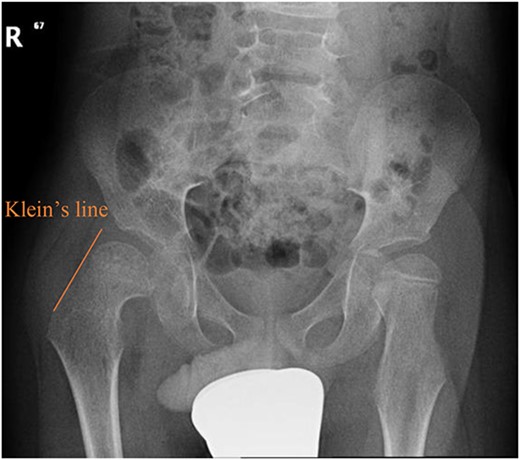

A 5-year-old independent ambulatory Middle Eastern boy with CP who was born preterm and developed grade III intraventricular haemorrhage and periventricular leucomalacia and was on AEDs, including valproic acid (VPA) and levetiracetam (LEV), for >3 years and was controlled over the last year (no history of seizure attack) presented to the emergency room (ER) with right hip pain and inability to bear weight for 4 weeks; the patient had no history of fever or trauma. Physical examination shows a thin, the weight is 12 kg, the height is 101 cm, vital signs within the normal range, tenderness over the right hip, and external rotation of the right hip, with restricted hip mobility. A radiological study was performed ~3 months before the patient presented to the ER for follow-up examination of a left hip coxa valgus deformity with no apparent abnormalities in the right hip (Fig. 1). Initial imaging studies conducted in the ER showed an anterior–posterior view of the pelvic radiograph, revealing Klein’s line [13] not intersecting the capital femoral epiphysis (Fig. 2), and frog-leg lateral view radiograph of the right hip (Fig. 3) confirmed SCFE and Southwick’s slip angle [13] of ~50° (moderate). Laboratory findings were clear for endocrine and renal diseases or infection, except for low vitamin D (total 25-OH Vitamin D: 43.4 nmol/L), suggesting vitamin D insufficiency. The diagnosis was confirmed with clinical and radiological studies as right-sided unstable SCFE requiring surgery. Surgical intervention was performed with percutaneous in situ fixation using a single fully threaded 4.5-mm cannulated screw (Fig. 4). Postsurgical rehabilitation included non-weight-bearing right lower extremities for 6 weeks. Regular follow-up with serial radiology studies showed stable fixation with no migration of screw or further slippage at 6 weeks (Fig. 5) and 3 (Fig. 6), 15 (Fig. 7), and 36 months (Fig. 8). During follow-up, a painless range of motion in the right hip was observed, with full weight-bearing and resumption of his usual activities with no complaints.

Pelvic anterior–posterior radiograph showing coxa valga deformity in the left hip.